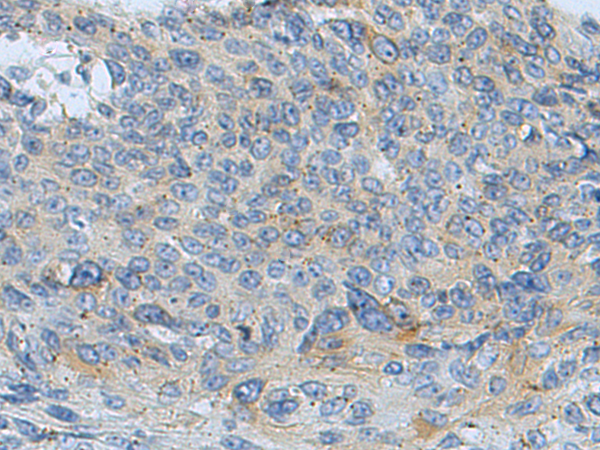

IHC positive control: |

Human thyroid cancer and Human liver cancer; Human cervical cancer |

IHC Recommend dilution: |

100-500 |